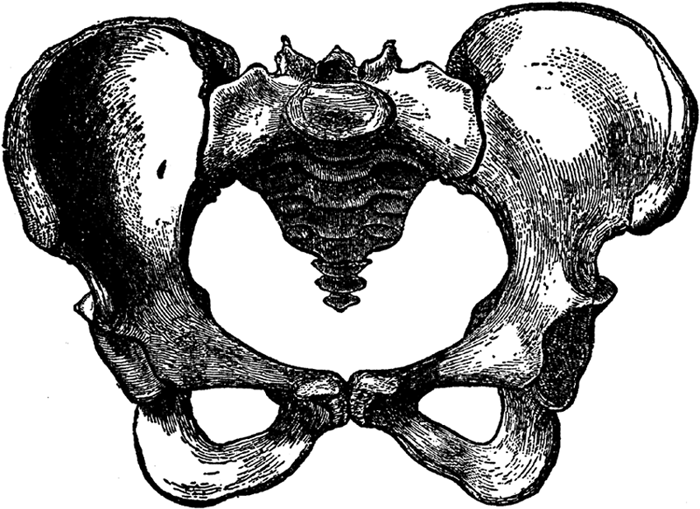

The Pelvis of the Female.

The internal sex organs are situated in the lower part of the abdominal cavity, the part that is called the pelvis, or pelvic cavity. The meaning of the word pelvis in Latin is basin. The pelvis, also referred to as the pelvic girdle or pelvic arch, forms a bony basin, and is composed of three powerful bones: the sacrum, consisting of five vertebræ fused together and constituting the solid part of the spine, or vertebral column, in the back, and the two hipbones, one on each side. The two hipbones meet in front, forming the pubic arch.

The hipbones are called in Latin the ossa innominata (nameless bones) and each hipbone is composed of three bones: the ilium, the ischium, and the os pubis. The thighs are attached to the hipbones, and to the hipbones are also attached the large gluteal muscles, which form the buttocks, or the "seat."

The pelvis of the female differs considerably from the pelvis of the male. The female pelvis is shallower and wider, less massive, the margins of the bones are more widely separated, thus giving greater prominence to the hips; the sacrum is shorter and less curved, and the pubic arch is wider and more [48]rounded. All this is necessary in order to permit the child's head to pass through. If the female pelvis were exactly like the male pelvis, a full-term living child could never pass through it. The two illustrations show the differences between the male and female pelvis very clearly.

Note particularly the differences in the pubic arches: in the male pelvis it is really more of an angle than an arch. Also note how much longer and more solid the sacrum (with its attached bone, called the coccyx[2]) is in the male pelvis. The differences in the pelves (the plural of pelvis is pelves) of the male and female become fully marked at puberty, but they are present as early as the fourth month of intra-uterine life.